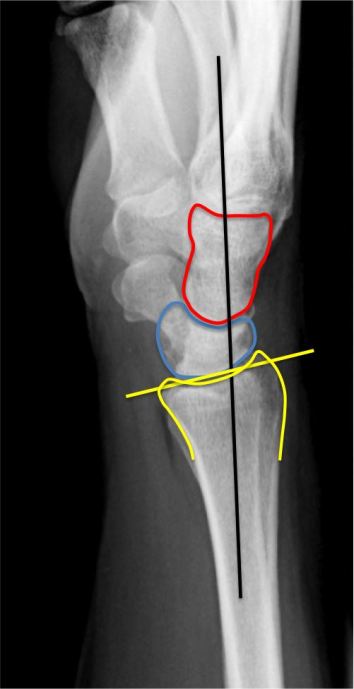

Finally the lateral view (or side-to-side) is used for only one purpose: does the capitate bone (or red cup) sit properly aligned with the lunate bone (or blue saucer) or is there a dislocation.